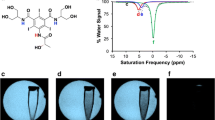

ASCT2 Expression Correlates with [18F]FGln Uptake

ASCT2 is differentially expressed in ccRCC cell lines (Fig. 1a). The cell line UMRC3, derived directly from the primary kidney tumor of a patient with metastatic ccRCC, showed higher expression than the normal kidney cell line HEK293 (Fig. 1b) and was amenable to siRNA knockdown of ASCT2. As a VHL mutant cell line, the UMRC3 cell line [26] is thought to be glutamine-dependent. UMRC3 cell injection into a nude or SCID mouse led to tumor formation and metastasis [27]. This cell line was used in all cellular and orthotopic in vivo experiments.

[18F]FGln uptake was dependent on ASCT2 expression. (a) ASCT2 expression was observed in multiple ccRCC cell lines. (b) Higher ASCT2 expression was observed in UMRC3 cells compared to HEK293 cells. This expression reduced in UMRC3 cells using siRNA. 1 h [18F]FGln uptake was higher in UMRC3 (c) than HEK293 (d) cells. For both cell types, addition of 50 μM V-9302 or 20 mM glutamine reduced uptake. Similar observations were made with 2-min uptake in UMRC3 (e) and HEK293 (f) cells. (g) siRNA-knockdown of ASCT2 reduced [18F]FGln uptake to the level achieved by 20 mM glutamine. (h) [18F]FGln uptake was increased with pre-treatment of UMRC3 cells with 3 µM CB-839 for 72 h. This increase was not observed when CB-839 was added to media just prior to the uptake experiment (0 h). All uptake experiments were analyzed using a one-way ANOVA with Dunnett’s multiple comparisons test, *** p < 0.001, ** p < 0.01, and * p < 0.05

[18F]FGln uptake in cells was performed by incubating one million cells for 2 min (transporter limited) or 1 h (steady state) with [18F]FGln, washing with cold PBS, and measuring cell-associated radioactivity on a gamma counter. Steady-state levels in UMRC3 cells showed tracer uptake was blocked by the addition of exogenous glutamine in the culture media (Fig. 1c). UMRC3 tracer uptake was twofold higher than non-cancerous HEK293 cells (Fig. 1c vs. Figure 1d). These trends were maintained with 2 min uptake experiments, albeit with lower total uptake (Fig. 1e-f). In each case, the addition of 50 µM V-9302, an ASCT2 inhibitor [12], significantly decreased [18F]FGln uptake by 20–50%, and addition of exogenous glutamine to the cell culture media significantly reduced uptake by 60–90%. In the UMRC3 cell line, [18F]FGln uptake was also reduced with siRNA knockdown of ASCT2 to the level obtained by the addition of exogenous glutamine (Fig. 1g). This confirmed the contribution of this transporter toward glutamine uptake. In contrast, an increase in [18F]FGln uptake was detected when UMRC3 cells were treated with 3 µM CB-839 for 72 h prior to uptake experiments (Fig. 1h). In addition, we observed higher expression of ASCT2 in UMRC3 cells treated for 65 h with 3 μM CB-839 compared to the vehicle (Supplemental Fig. 3a). These results were in agreement with similar [18F]FGln uptake studies [18, 19].